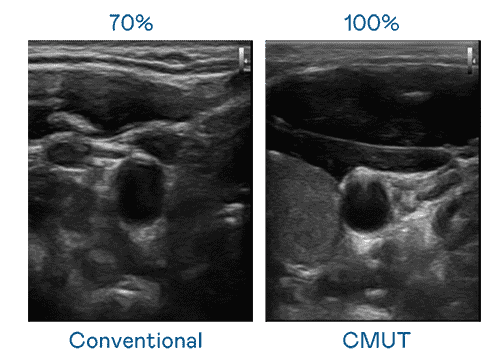

CMUT 技术是一种用电容式微机电元件来产生超音波讯号的技术。。。。与传统 PZT 压电式技术相比,,,CMUT 频宽增加 30%,,更宽频的超音波讯号让影像解析度大幅提升,,,是实现高影像品质医疗超音波扫描、、、、促进精准医疗发展的关键技术。。。。

大频宽带来超清晰影像

超音波影像的解析度高低,,,,首先取决于探头能发出的讯号频宽。。菠菜论坛 CMUT 可提供高清晰的超音波讯号,,提供高频宽、、、、高灵敏度、、、影像纹理细节更高的超音波影像,,,,协助医护人员缩短影像判读时间及利用精准的医疗影像进行诊断。。